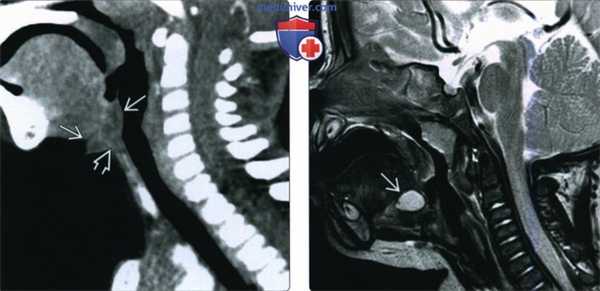

(Слева) При сагиттальной КТ с КУ у ребенка с рецидивирующей кистой щитоязычного протока в надподъязычном отделе шеи по средней линии визуализируется объемное образование неоднородной структуры с бугристыми краями, наличие которого позволяет предположить воспаление остатка щитоязычного протока. Обратите внимание, что средняя часть подъязычной кости отсутствует, что связано с ранее выполненной операцией Систранка.

(Справа) При сагиттальной МРТ Т2ВИ у ребенка, которому данное исследование было выполнено из-за судорожных припадков в корне языка по средней линии визуализируется случайно выявленное объемное образование с гиперинтенсивным сигналом, которое впоследствии было верифицировано как КЩЯП.